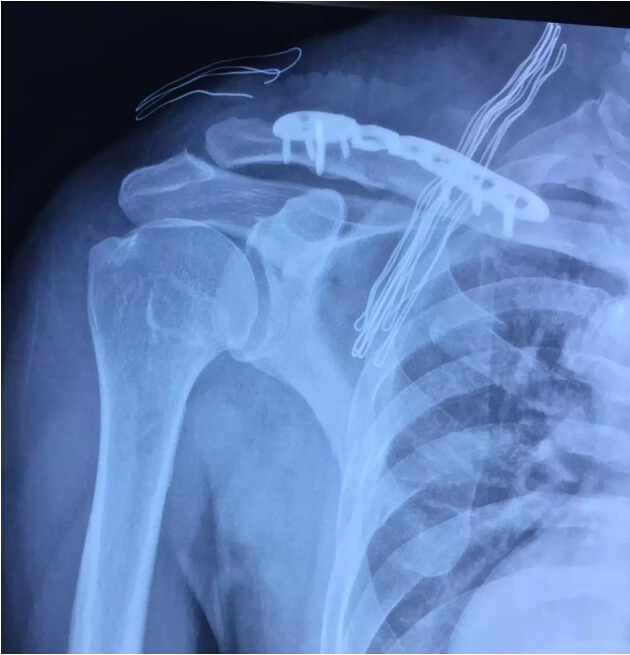

術(shù) 后